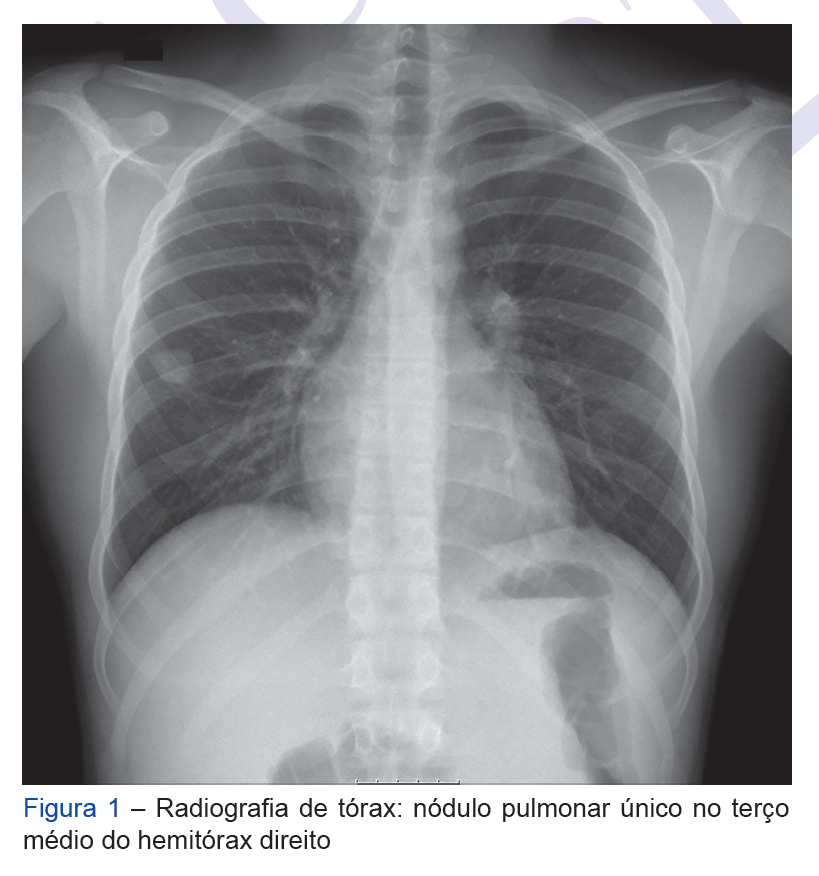

Primary lung tumors in the pediatric age group are rare, histologically diverse and have different therapeutic approaches. The inflammatory myofibroblastic tumor ...